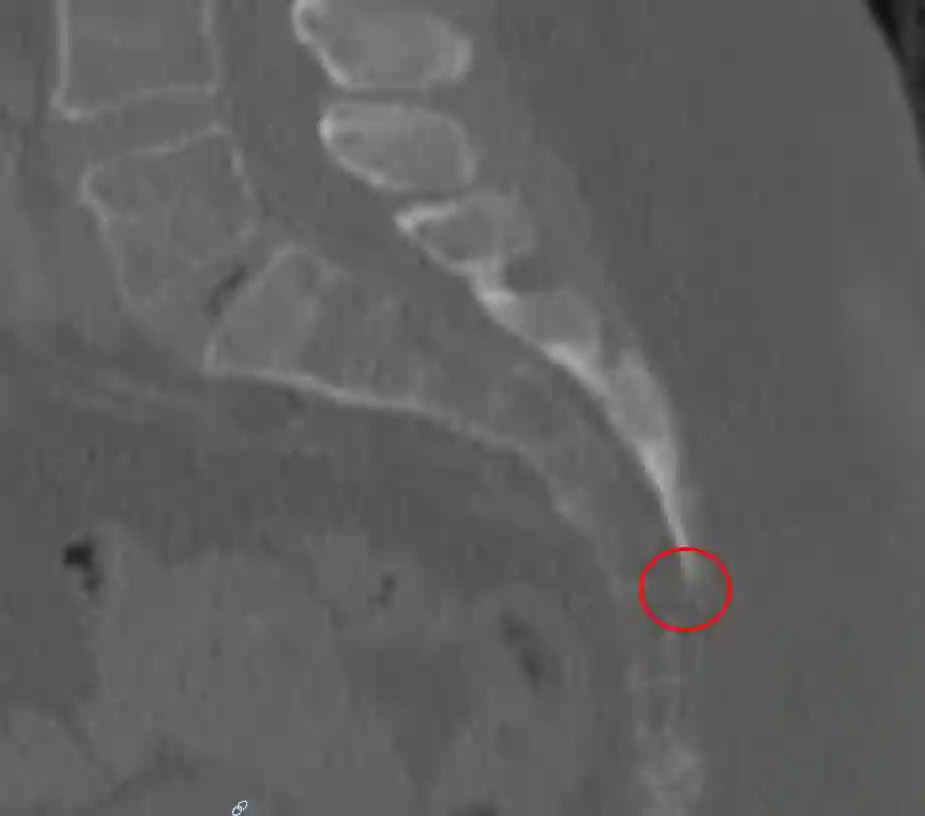

Hiatus sacralis im CT

Darstellung des Hiatus sacralis (roter Kreis) des Os sacrum in einer sagittalen CT Aufnahme im Knochenfenster.